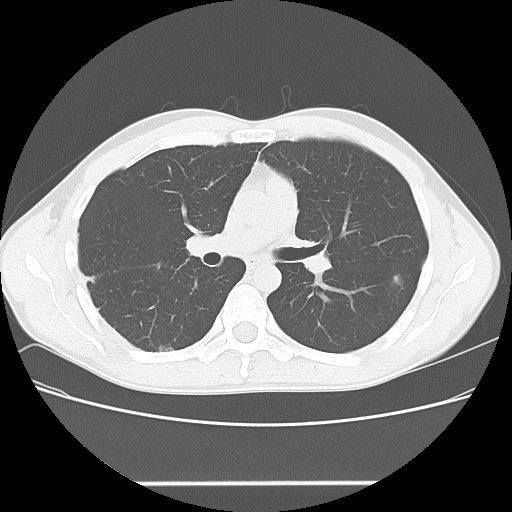

2006年入院治療の退院日から10年。 かなり大きな節目なんだが、なんだろうこの軽い感じは(笑)。 「10年生きたんだぁ」くらい。 変わったような変わっていないような。 当時は10年後なんて全く考えていなかった。 今も10年後は考えていないが・・・。 退院前日の2006/10/31は46.6kgだった。 今日計ったら54.8kg。体脂肪は16.6%。 とても健康にストレスなく生活できていることに、治療当時から現在に至るまで、関わった人全員に感謝の気持ちです。 マーカー、CT画像、問題なし!! 血液検査結果もほとんど文句なしの正常値。 そうだなぁ、数値に出ない異変としては、肩凝りかなぁ。 一旦夏になくなったと思ったが、初秋から再発。 マウスを左手にしたり、シップ貼ったり、最近はホッカイロ貼ったり。 で、一向に良くなる気配がない。 やはり四十肩なのか。 でも肩の可動域は問題ない。動かせないような痛みも無い。 結局色々考えてたどり着いたのは「変形性頚椎症」ではないかと。 肩凝りや頭痛がダラダラと続くようになるという症状がピッタリ当てはまる。 さて、改善策がなかなか難しい。 整形外科行ってもレントゲン撮って湿布をくれるだけだろう。 そんなことに大金を出すならまずは300円/回のプールで泳ごうと思う。 重力から開放して全身運動をするのが一番良いらしい。 2015年の目標は少しでも良いから水泳を再開する、だな。 マーカー、CT画像、問題なし!! 通常の血液検査結果も文句なしの正常値がズラ~っと並んだ!! 間違いなくヨメの食事のおかげである。ほんとうに感謝である!! ちなみに最近少々腰周りの肉付きが気になっていたのだが・・・。 左から2013年12月、2013年06月、2012年12月と背骨の位置は合わせて並べてみた。 6月まではあまり変化がなかったが、この半年で明らかに違う。 背中側の脂肪がやや増えてはいる。 でも最も大きな違いは、腸なのか、やたらと内臓が膨れている・・・。 一言で言うと食べすぎ?!?! 食事は野菜中心ではあるが、確かによく食べているw。 せっかくスーツのウエストを詰めたんだからこれ以上にならないようにしたい。 「腹八分目を心がける」かな。